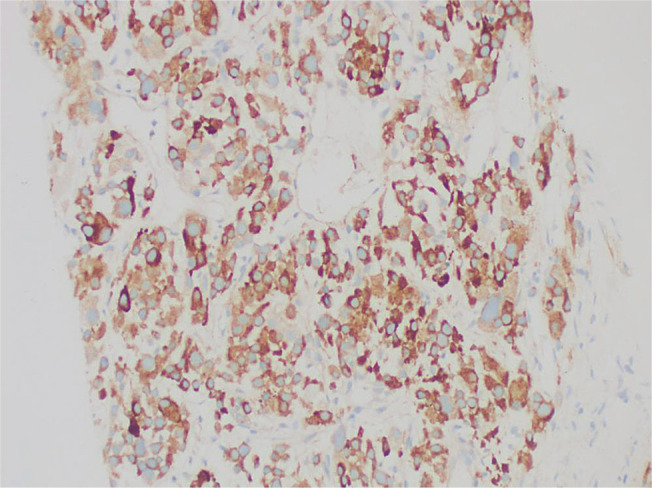

Adrenocortical carcinoma (ACC) is a rare malignant tumour from the adrenal cortex. Half of the cases are functional, with ACTH-independent autonomous cortisol production being the most common. It is rare for ACC to present with markedly elevated metanephrine levels, characteristic of pheochromocytoma. We report a case of a large functioning adrenal tumour with overlapping biochemical features of ACC and pheochromocytoma. Biopsy confirmed the histopathological diagnosis of metastatic ACC.